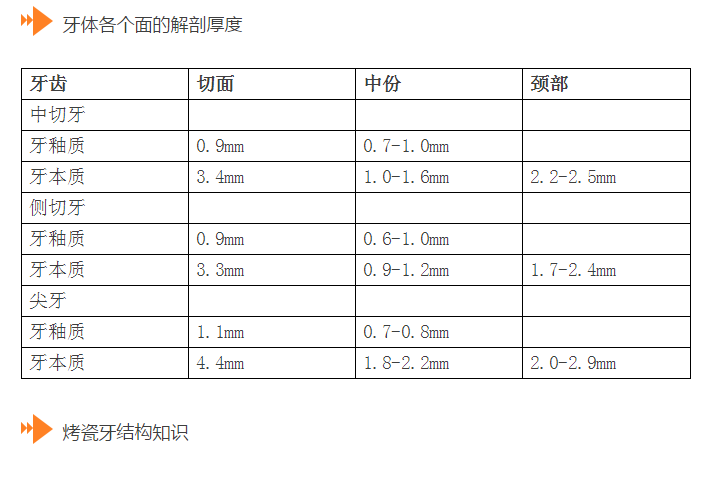

l保護牙體組織

l預留修復體的空間

l防止過度預備(造成牙髓激惹)

l保留活髓(保留牙體的整體性和韌性)

l過度預備抗力形喪失